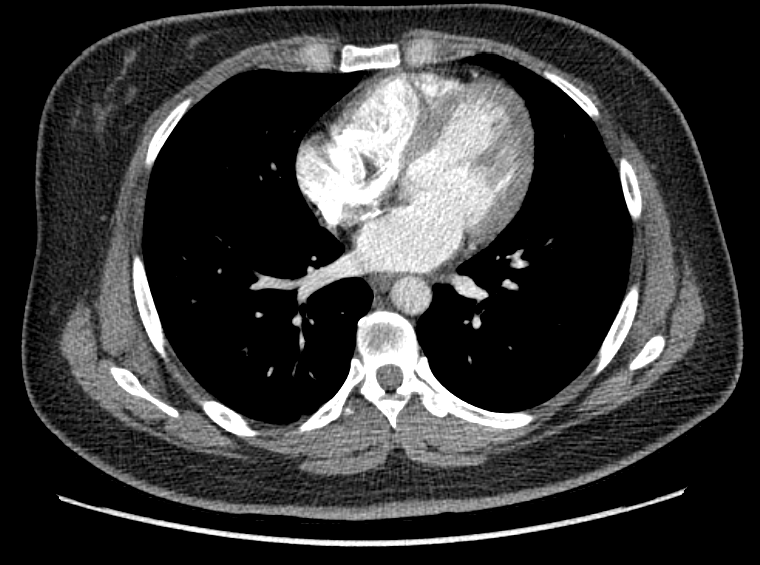

F/34

°Ç°­°ËÁø»ó ½ÃÇàÇÑ Chest PA »ó mediastinal widening ¼Ò°ßÀ¸·Î further evaluation À§ÇØ ³»¿øÇÔ.

Áõ»óÈ£¼Ò ¾øÀ¸¸ç ½Åü°ËÁø»ó ƯÀÌ¼Ò°ß ¾øÀ½.